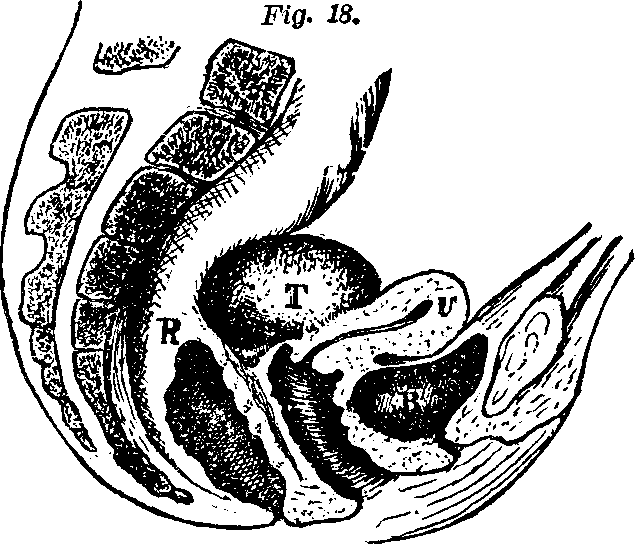

Fig. 10. Flexion, u, Uterus, B, Bladder.

Fig. 11. Version, u, Uterus, B, Bladder.

Flexions and Versions of the Womb. Flexion of the uterus, in which it is bent upon itself, as illustrated in Fig. 10, produces a bending of the cervical canal, constricting or obliterating it, and thus preventing the passage of spermatozoa through it. Version of the uterus [pg 710]in which its top, or fundus, falls either forward against the bladder (anteversion), as illustrated in Fig. 11, or backward against the rectum (retroversion), may close the mouth of the uterus by firmly pressing it against the wall of the vaginal canal, and thus prevent the passage of spermatozoa into the womb. 'The treatment of these several displacements will be considered hereafter. We may here remark, however, that they can be remedied by proper treatment. Our mechanical movements, manipulations, and kneadings are invaluable aids in correcting these displacements.